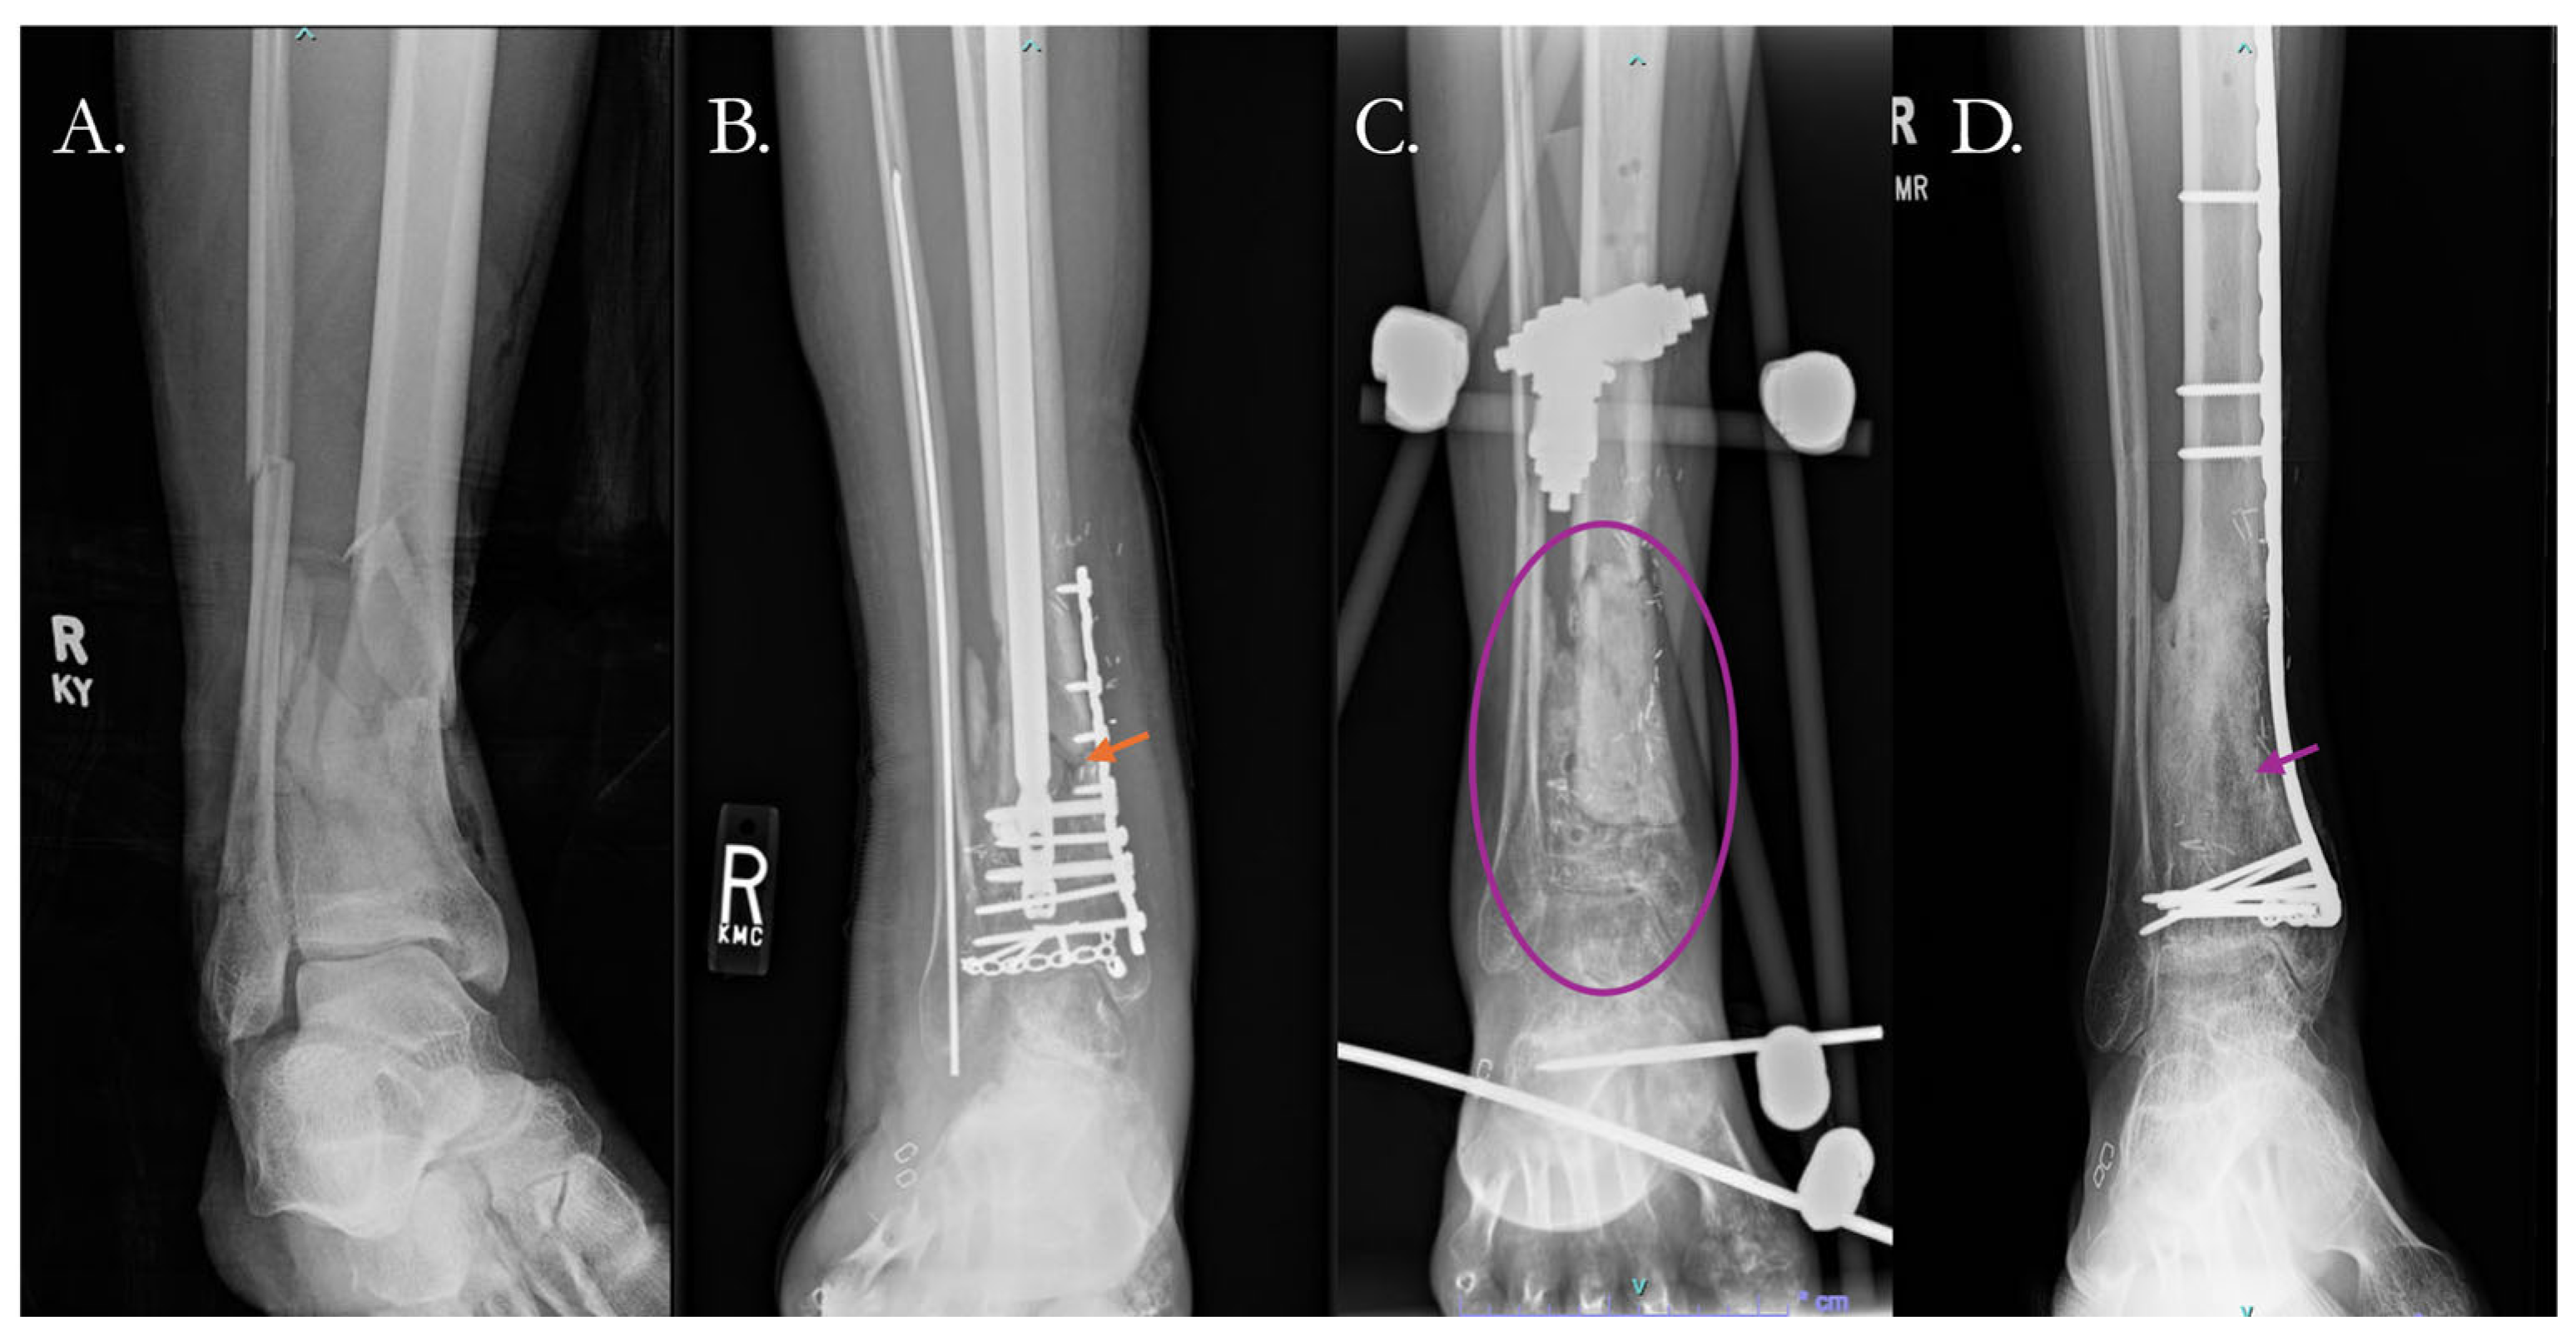

4.2.1. Traditional Surgical Approaches

- Alford, A.I.; Nicolaou, D.; Hake, M.; McBride-Gagyi, S. Masquelet’s Induced Membrane Technique: Review of Current Concepts and Future Directions. J. Orthop. Res. 2021, 39, 707–718. [Google Scholar] [CrossRef] [PubMed]

- Hoit, G.; Kain, M.S.; Sparkman, J.W.; Norris, B.L.; Conway, J.D.; Watson, J.T.; Tornetta, P.; Nauth, A. The Induced Membrane Technique for Bone Defects: Basic Science, Clinical Evidence, and Technical Tips. OTA Int. 2021, 4, e106(1–5). [Google Scholar] [CrossRef] [PubMed]

- Chloros, G.D.; Kanakaris, N.K.; Harwood, P.J.; Giannoudis, P.V. Induced Membrane Technique for Acute Bone Loss and Nonunion Management of the Tibia. OTA Int. 2022, 5, e170. [Google Scholar] [CrossRef]

- Griffin, J.T.; Landy, D.C.; Sneed, C.R.; Liu, B.; Kavolus, M.; Pectol, R.W.; Gitajn, I.L.; Oh, J.-K.; Aneja, A. Masquelet Technique for the Tibia: A Systematic Review and Meta-Analysis of Contemporary Outcomes. J. Orthop. Trauma 2023, 37, e36–e44. [Google Scholar] [CrossRef]